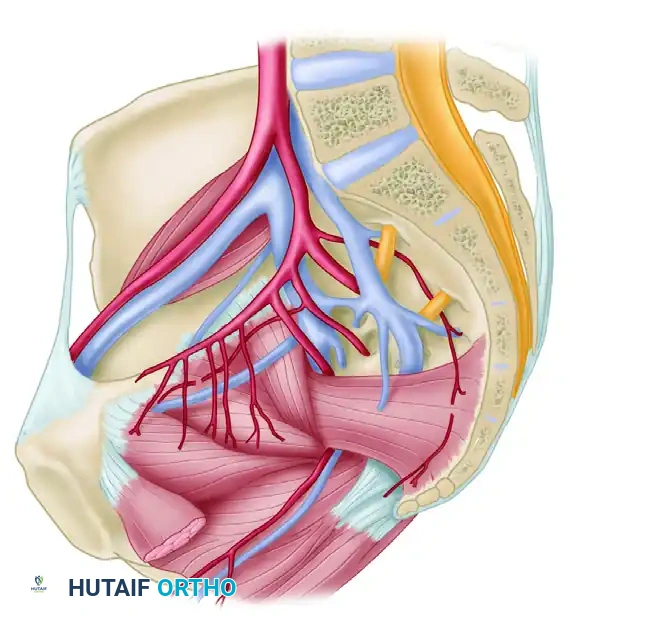

Vascular Anatomy

The internal iliac plexus of arteries and veins lies in intimate proximity to the anterior sacrum and sacroiliac joints. Disruption of the posterior ring frequently tears the thin-walled presacral venous plexus, leading to massive retroperitoneal hemorrhage. Arterial bleeding, typically from the superior gluteal or internal pudendal arteries, occurs in approximately 10-15% of hemodynamically unstable patients and requires emergent angioembolization.